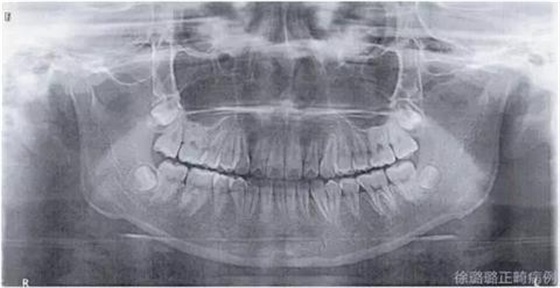

影像學檢查

360截圖20170120124727674.jpg

X 線檢查:替牙列,上頜雙側(cè)尖牙埋伏阻生(含牙囊腫),四顆第三恒磨牙牙胚存在。

前牙 CT 檢查:上頜雙側(cè)尖牙埋伏阻生——雙側(cè)尖牙的牙冠均在側(cè)切牙根方的唇向位。